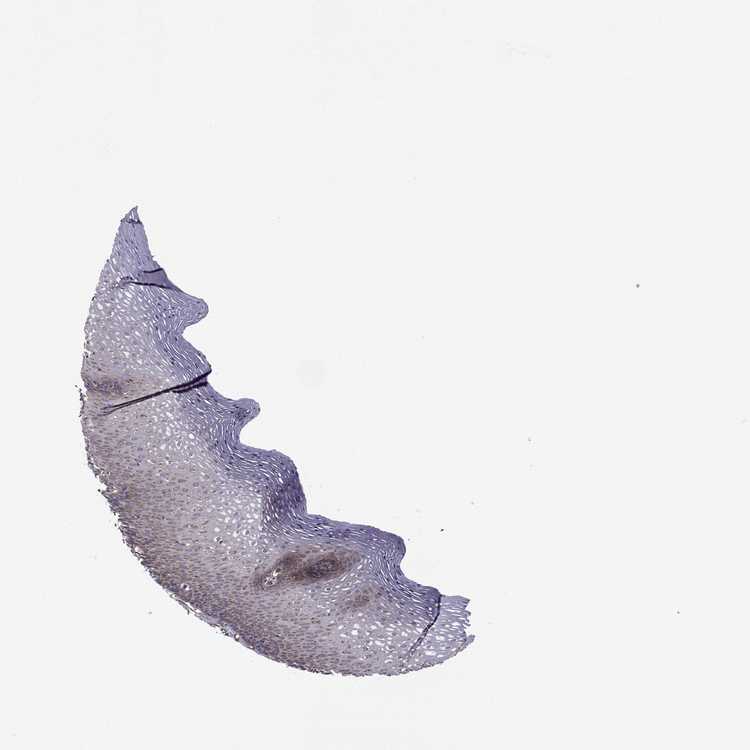

TISSUE PRIMARY DATA ESOPHAGUS Show tissue menu

ESOPHAGUS - Antibody stainingi

Antibody staining in the annotated cell types in the current human tissue is reported as not detected, low, medium, or high, based on conventional immunohistochemistry profiling in selected tissues. This score is based on the combination of the staining intensity and fraction of stained cells.

Each image is clickable and will lead to virtual microscopy that enables deeper exploration of all samples and also displays staining intensity scores, fraction scores and subcellular localization as well as patient and tissue information for each sample.

Antibody HPA038149Antibody HPA038150

Squamous epithelial cells MediumHigh